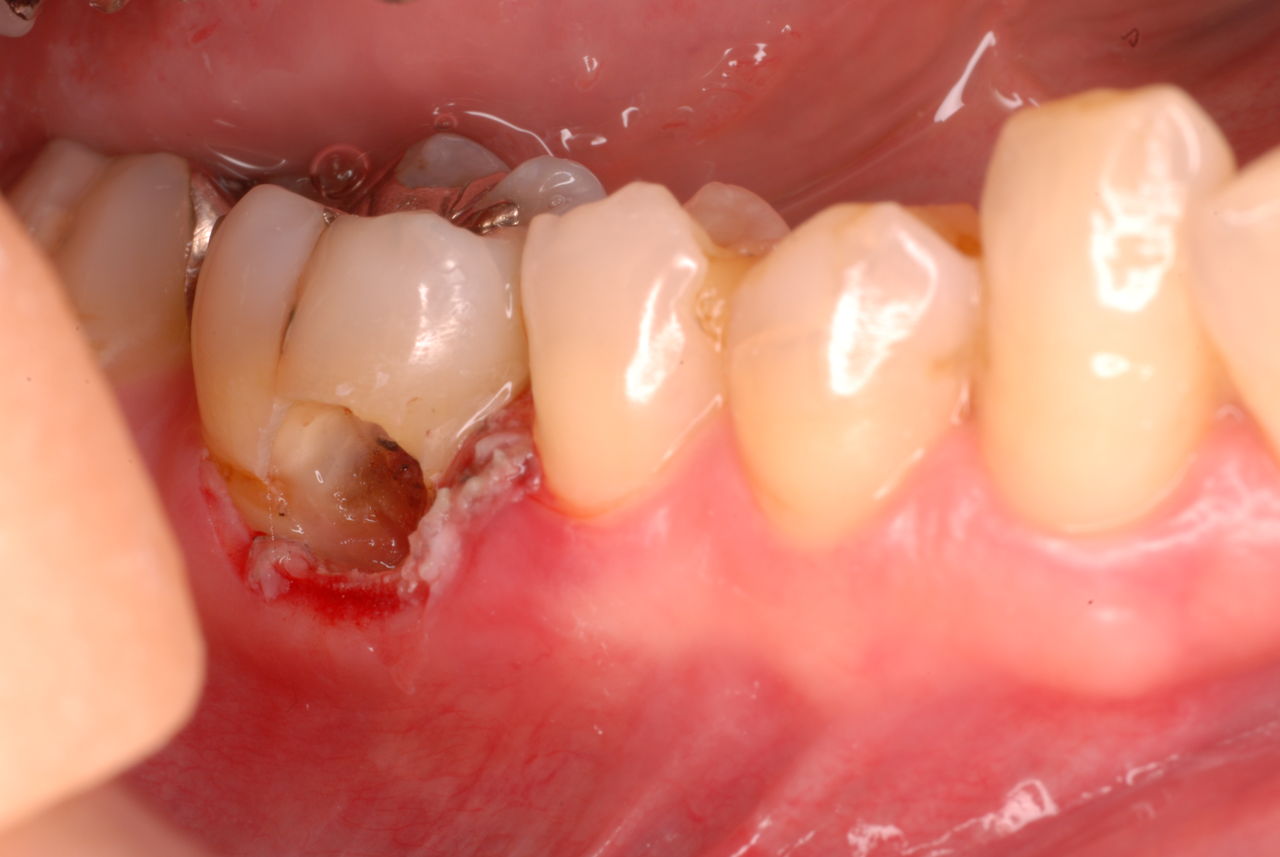

相談しても“問題無い”の説明だけだそうです。調べたところ歯周病は進行しているし、奥歯の大きい歯2本ずつ計4本はしっかり噛んでいないのです。よく噛めないというのはそのことのようでした。これを矯正的に元に戻すことはできない訳ではありませんが、時間と手間がかかるのは間違いないことです。

歯を削らないといいましても結局歯の間を削りスペースを確保したそうですから、何らかの歯に対する傷害はしているのです。それは虫歯や歯周病を起こしやすい理由にもなりますからこれからも要注意なのです。二年間という貴重な時間を費やしていますから患者本人は大変だったと思います。そして二年間を要したならば更に二年間動かないようにするための入れ歯やマウスピースを装着し続けなければいけないのです。